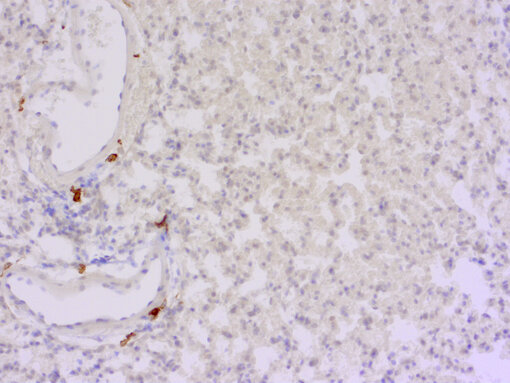

CD163 positive interstitial macrophages in FFPE mouse lung section.

Figure 9: Staining for rabbit CD163 (HS-455 003, 1:250) in formalin fixed paraffin-embedded mouse lung shows CD163-positive interstitial macrophages, whereas alveolar macrophages are CD163-negative. Nuclei have been counterstained with haematoxylin (blue).

Interstitial macrophages derive from bone-marrow after birth (Akata et al., 2020) and replace embryonic primitive interstitial macrophages that preferentially localize to the peripheral and perivascular regions in the adult mouse (Tan et al., 2016). Interstitial macrophages are CD11bpos  SiglecFneg CD11clow CCR2low CX3CR1pos (Schyns et al., 2018) and comprise several subsets that are associated to blood vessels (Chakarov et al., 2019) or to airway-associated nerves (Ural et al., 2020). In contrast to alveolar macrophages, interstitial macrophages highly express monocyte-related genes, such as CD14, Csf1r and CD163 (figure 9) (Gibbings et al. 2017). IBA1 is high in interstitial macrophages but low in alveolar macrophages (Donovan et al., 2018). F4/80 expression in embryonic primitive macrophages and in bone-marrow derived interstitial macrophages is down-regulated in postnatal life (Tan et al., 2016).